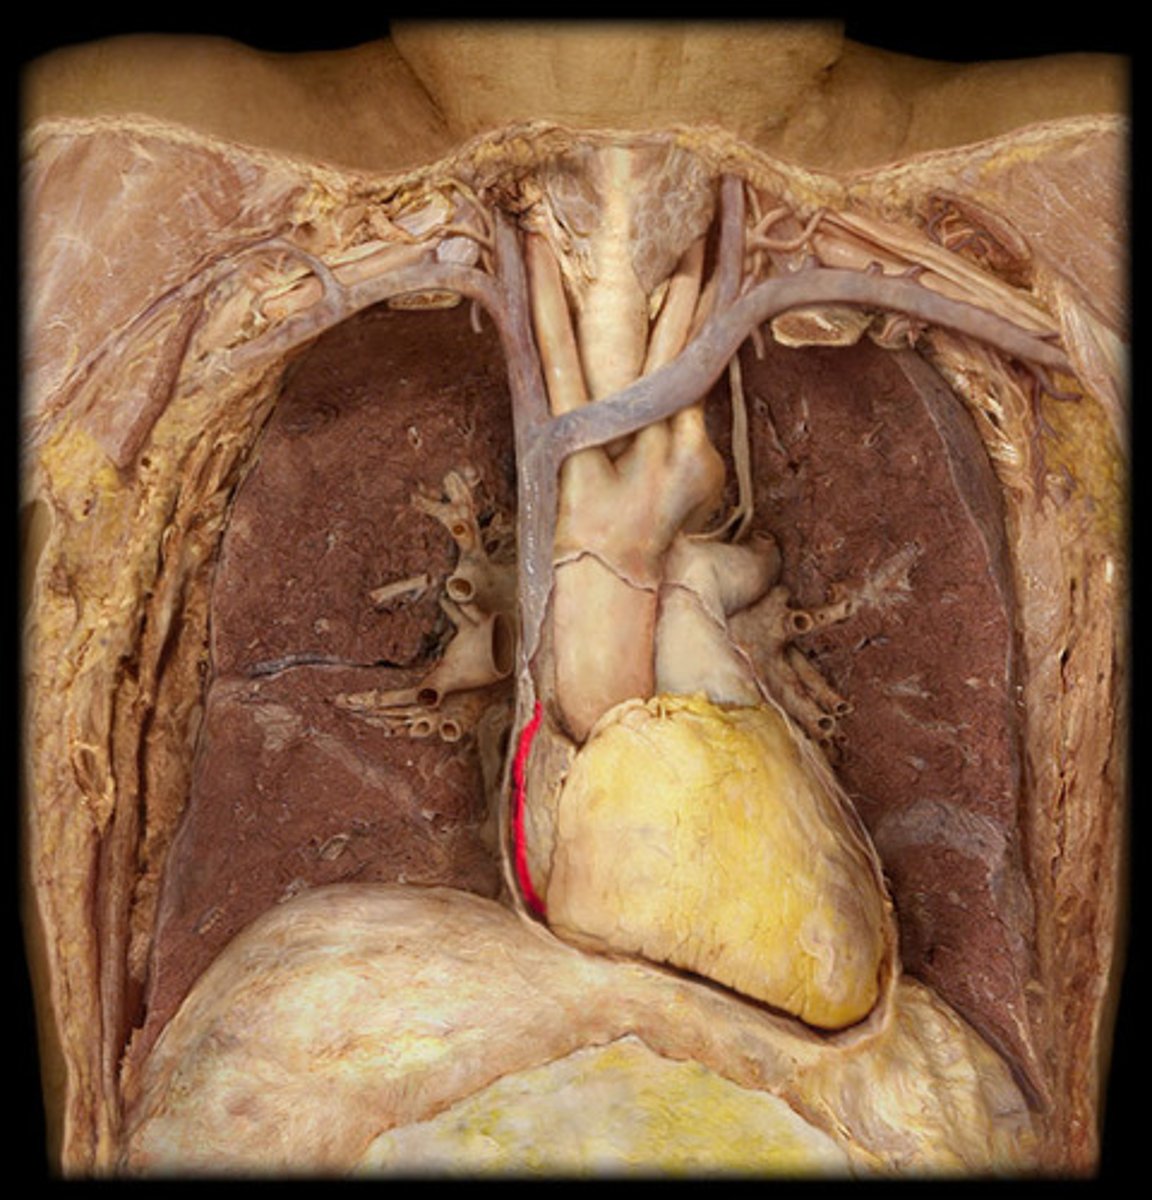

anterior surface of the heart

Region; hold heart where it sits in chest, wave hand in front

Diaphragmatic surface of the heart

Region, hold heart where it sits in chest, wave hand below it

R. pulmonary surface of the heart

Region; hold heart where it sits in chest, wave hand on medial side

L pulmonary surface of the heart

Region; hold heart where it sits in chest, wave hand on lateral side

Right border of the heart

Boundary; X-ray, medial edge

L border of the heart

Boundary, X-ray, lateral edge, apex points this way

Inferior border of the heart

Boundary; X-ray, bottom edge

Superior border of the heart

Boundary; X-ray, top edge

Aorta

Structure, big tube off heart with the “fingers”

Pulmonary trunk

Collective structure; under aorta, splits into 2

Superior vena cava

st

Posterior side, probe from above on right

inferior vena cava

Posterior side, probe from below on right